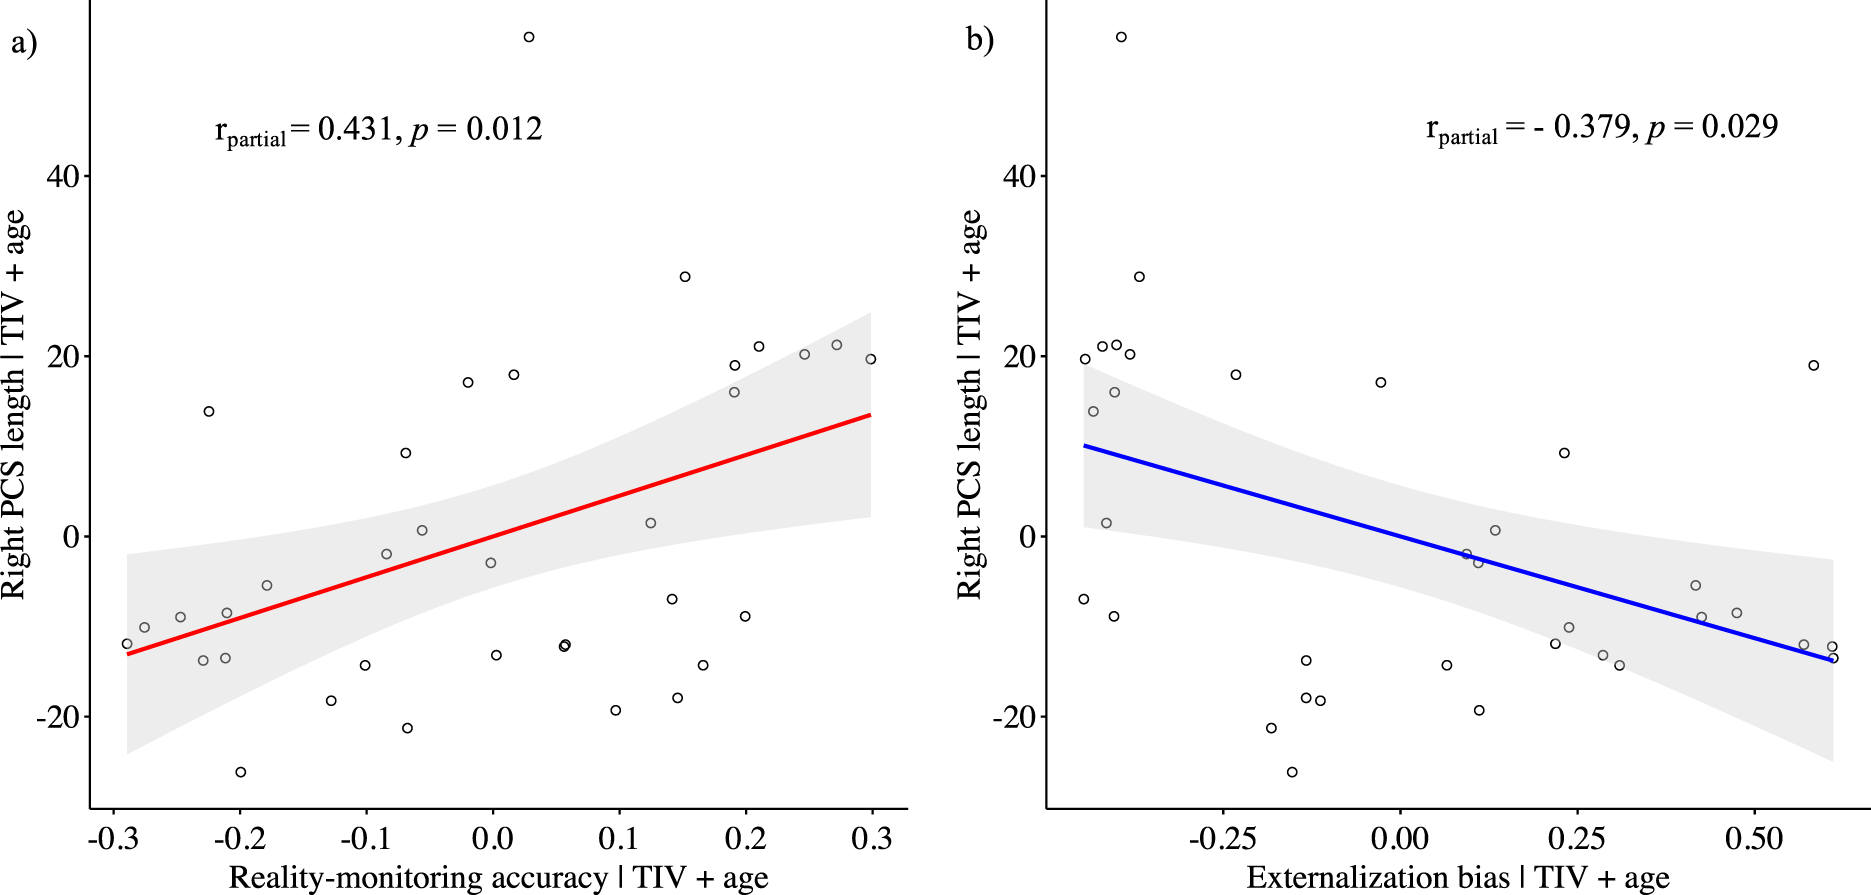

While controlling for age and total intracranial volume, the PCS length was positively correlated with reality-monitoring accuracy in the right hemisphere (Spearman’s partial ρ = 0.431, p = 0.012; Figure 2A) but not in the left hemisphere (Spearman’s partial ρ = 0.052, p = 0.773). There was a significant negative correlation between the length of the right PCS and the externalization bias (Spearman’s partial ρ = −0.379, p = 0.029; Figure 2B), but no significant correlation was found for the left PCS length and the externalization bias (Spearman’s partial ρ = 0.171, p = 0.340). No significant correlations were found between PCS lengths and item memory (for the right PCS: Spearman’s partial ρ = 0.137, p = 0.448; for the left PCS: Spearman’s partial ρ = −0.003, p = 0.988).

Figure 2. Scatter plots showing the partial correlations between the paracingulate sulcus length in the right hemisphere and (A) reality-monitoring accuracy and (B) the externalization bias, controlling for total intracranial volume and age (n = 35).